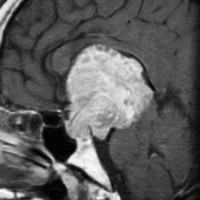

典型的なMRIの画像です

下垂体腺腫のMRIです。両側の視野障害(両耳側半盲)のために手術を受けた患者さんのものです。この腫瘍は非機能性腺腫といってホルモンを出さない腫瘍でした。少し大きめでしたが全部取れて視野の障害はよくなりました。

左の2枚はガドリニウム造影剤を使って写したもので腫瘍の形がよくわかります。右の1枚はT2強調画像と言います。MRIでは撮影の仕方によって見え方が違います。